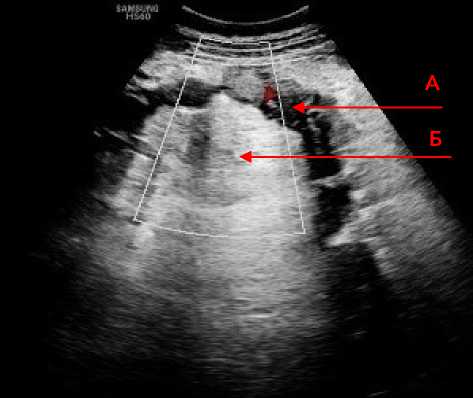

В поздние сроки (7–21 сутки) в трёх случаях лоцировался фрагмент тонкой кишки с отёком стенки пониженной эхогенности с мелкими гиперэхогенными включениями в структуре – пузырьками газа (рис. 3).

Рисунок 3. Эхограмма фрагмента подвздошной кишки с отёком стенки ( А ) и мелкими гиперэхогенными включениями в структуре стенки ( Б )

Figure 3. Echogram of a fragment of the ileum with wall edema ( A ) and small hyperechoic inclusions in the wall structure ( Б )